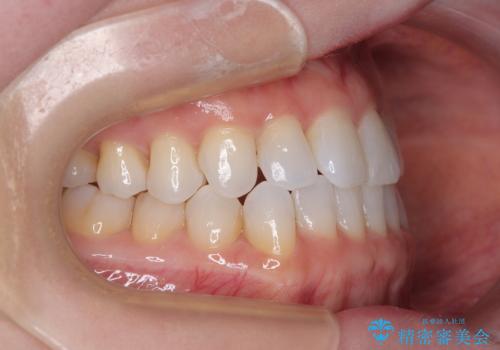

前歯のデコボコをインビザラインで綺麗に

- 上下前歯の叢生を気にして来院された患者様です。

インビザラインでの治療を希望されていて、デコボコの程度が中等度であり、安価なパッケージにて対応可能と判断されたため、インビザライン・モデレートを用いて矯正治療を行うこととしました。

インビザライン・モデレートは、製作できるアライナーの枚数に制限があるため、移動可能な量に限りがあるものの、インビザライン・ライトよりも枚数が多いため、幅広い症例に対応可能です。